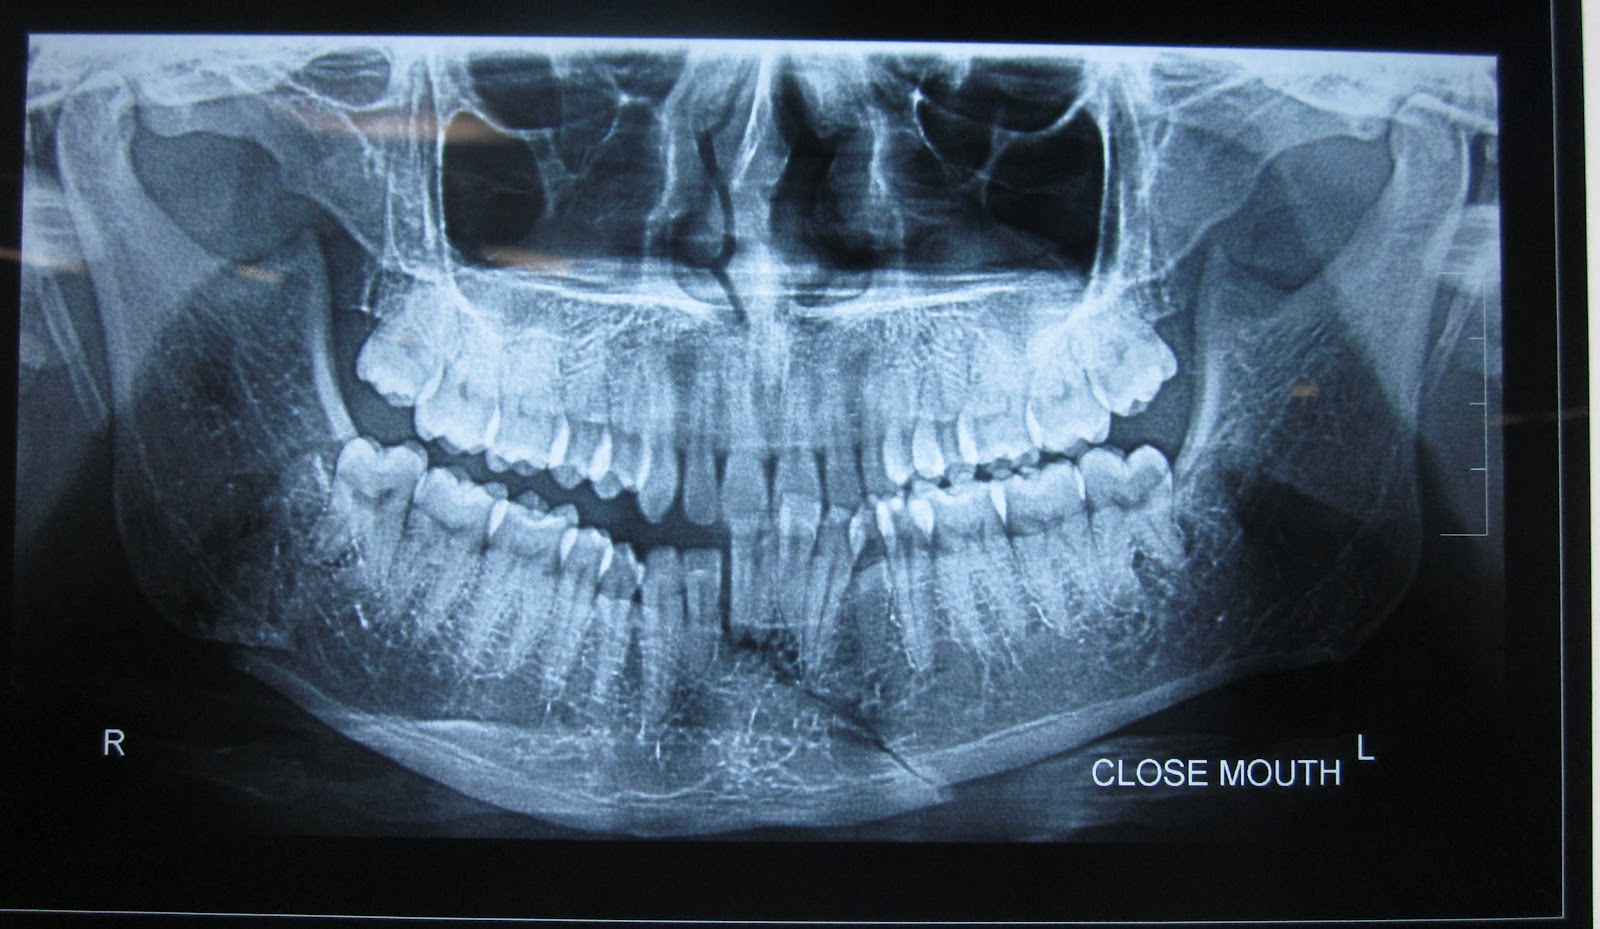

Fractures of the mandibular body may be classified by anatomic location, condition, and position of teeth relative to the fracture, favorableness, or type. The treatment of mandibular angle fractures also traditionally involves maxillomandibular fixation (mmf). Dr sunil richardson shows the various steps involved from seeing.

Reis, thiago vinicius rodrigues dds†; 가천의과대학교 길병원 구강악안면외과 전 창 훈. The mandibular fracture has typical curves of the fracture lines that run along weaknesses of the mandible. Anterior border of masseter to posterosuperior attachment of masseter. Mandibular fractures are relatively common especially among young men. Reis, thiago vinicius rodrigues dds†; Fractures of the mandibular body may be classified by anatomic location, condition, and position of teeth relative to the fracture, favorableness, or type. Although traditionally the mandible and base of skull are thought to form a complete bony ring, interrupted only by the tmjs. Rebellato, nelson luis barbosa dds, phd∗; .fractures, and the angle region represents 32% of the mandibular fractures; Learn vocabulary, terms and more with flashcards where is an angle mandibular fracture? A number of reviews have suggested that the presence of a. Management of mandibular angle fractures is often challenging and results in the highest complication rate among fractures of the mandible. Learn about the mandible jaw bone anatomy including parts of the mandible. A retruded chin can be caused by bilateral parasymphyseal fractures. By amrish bhagol, virendra singh and ruchi singhal. Mandibular fracture, also known as fractures of the jaw, are breaks through the mandibular bone.